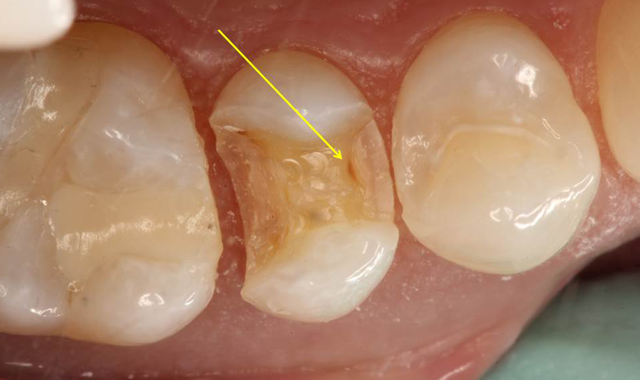

Fig. 5a #4 mesial decay

Based upon the patient’s history, compliance and desire to avoid costly dental treatment, a preventive treatment option was offered in an attempt to remineralize the interproximal lesions. The protocol involved an office fluoride varnish application with 3M ESPE Vanish Varnish and use of 3M ESPE Clinpro 5000 toothpaste at home. The areas were rescanned with The Canary System 6 months later with no reduction in the CN. Further review of risk factors revealed that the patient continued to consume one to two carbonated sugared drinks per day, which likely interfered with the remineralization process. Based upon the Canary findings, tooth #4 underwent restorative treatment. As soon as the mesial portion was opened, a large lesion was found which extended beyond the DEJ (Fig. 5a). Visual examination of the distal surface of tooth #5 revealed an area of brown decalcification with no obvious pathology (Fig. 5b). The distal surface of tooth #5 was opened (indicated with a yellow arrow) and a large lesion into the dentin was found (Fig. 5c).